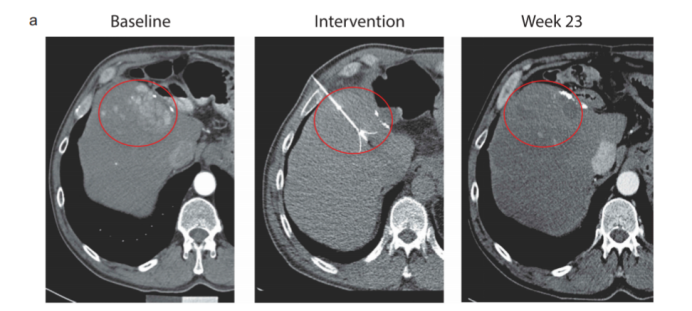

自2006年世界上第一个癌症疫苗——宫颈癌疫苗获得美国食品药品管理局(FDA)的批准上市以来,针对癌症疫苗的研究从未停止。目前,癌症疫苗可分为预防疫苗和治疗疫苗。预防疫苗最常见的就是HPV疫苗,而治疗疫苗目前也有不少进入临床。今天,我们就带大家看一下在肝癌领域,有哪些治疗性疫苗取得了不俗的疗效! 癌症治疗疫苗提高了免疫系统识别和摧毁抗原的能力。通常, 癌细胞在其表面上有某些分子被称为癌症特异抗原, 而健康细胞没有。当这些分子被赋予一个人时, 分子就会充当抗原。它们刺激免疫系统, 以识别和摧毁在其表面上有这些分子的癌细胞。大多数癌症疫苗也含有佐剂, 这些药物可以帮助增强免疫应答。 治疗性疫苗包括多肽、树突状细胞(DCs)、全细胞疫苗、溶瘤病毒和DNA制剂,这些可增加或实现对肿瘤抗原的特异性免疫应答。目前,一些多肽,如甲胎蛋白(AFP)、多药耐药相关蛋白3 (MRP3)和糖基蛋白3 (GPC3),已经被检测并被证明具有良好的耐受性和安全性。 甲胎蛋白(AFP)是肝细胞癌(HCC)中过表达的一种胎儿癌抗原。之前的研究证明,从AFP获得的HLA-A2限制性表位在体内外均具有免疫原性。研究人员利用先前鉴定的人AFP肽表位,创建了一种AFP表达的复制缺陷腺病毒,作为基于T细胞的免疫治疗的潜在靶点。 因此,作为一项I/II期试验(NCT00093548)的一部分,筛选有AFP+肿瘤且曾接受过HCC治疗的HCC患者,其中2例接受了疫苗接种。该临床试验表明,第一个病人有微弱的AFP特异性T细胞反应,并在9个月后复发,出现AFP表达的HCC。而第二个患者第二例患者出现了强烈的AFP特异性CD8+和CD4+细胞反应和AdV中和抗体反应,18个月后复发,血清AFP没有增加。此外,该疫苗具有良好的耐受性和安全性,没有明显的临床不良事件。这两名患者的观察结果支持在更大规模的临床试验中开发这种疫苗策略。 Glypican-3 (GPC3)是HCC组织中过表达的一种蛋白,但在健康成人肝脏中不存在。到目前为止,针对Glypican-3的各种免疫疗法已经被开发出来。 在一项I期临床研究(UMIN000001395)中,33例晚期HCC患者使用了GPC3衍生的肽疫苗,1例患者在开始治疗2个月后出现部分缓解,19例患者病情稳定。整体ORR为91%,中位PFS为3.4个月,中位OS显著改善,为9.0个月(95% CI: 8.0-10.0)。且CTL频率与OS显著相关,≥50为12.2个月,<50为8.5个月(P=0.033)。此外,与GPC3特异性细胞毒性T淋巴细胞(CTL)较少的患者相比,接种疫苗后GPC3特异性CTL增加,且报道显示疫苗耐受良好。 另一项II期研究结果显示,GPC3阳性患者接受辅助疫苗接种后,整体中位OS为20.1个月。41例接种疫苗的患者1年和2年的复发率为分别为24.4%和53.7%。与仅接受手术的80例患者相比,41例手术或射频消融联合疫苗接种的复发率更低(1年复发率24.4% vs 42.5%,p = 0.054;2年复发率53.7% vs 66.2%,p=0.198)。 多药耐药相关蛋白3 (MRP3)是一种载体型转运蛋白,是ATP结合盒式(ABC)转运蛋白的成员,其高表达与多种癌细胞相关。HCC组织中MRP3表达水平升高,显著高于非癌组织(p < 0.05)。无论肝功能、HCV感染状态、AFP水平和HCC分期如何,MRP3特异性CTL均可被激活。此外,研究证明MRP3在对索拉非尼毒性耐受的肝癌细胞中发挥重要作用,因此,MRP3是HCC免疫治疗中具有强免疫原性的肿瘤抗原的潜在候选抗原。 一项I期临床试验(UMIN000005678)研究了MRP3来源肽(MRP3765)作为疫苗在12例HLA-A24阳性HCC患者中的安全性和免疫原性。免疫耐受良好,整体ORR为72.7%,中位OS为14.0个月(95%CI:9.6~18.5)。 树突状细胞(DCs)是APCs,负责刺激T细胞和增强抗肿瘤免疫反应。树突状细胞在体外成熟和活化后被注射回病人体内。使用装载肿瘤细胞裂解物的树突状细胞疫苗的研究在小鼠模型中显示了抗肿瘤作用。与此同时,DC来源的外泌体形成了一类新的癌症免疫治疗疫苗,可触发强的抗原特异性抗肿瘤免疫反应,重塑肿瘤微环境。 一项I期研究对不能切除的原发性HCC患者进行自体树突状细胞免疫治疗,以评估免疫治疗的安全性和可行性。在这项研究中,80%的患者为肝细胞癌,而其余的患者则为胆管癌。作者报告免疫接种在所有患者中耐受良好,且未检测到明显的毒性。此外,一名患者的肿瘤缩小并在CT上显示坏死改变,而另外两名患者的血清肿瘤标记物水平在接种疫苗后下降。 另一项II期临床试验评估了肿瘤细胞裂解物致敏的树突状细胞(DC)作为佐剂对肝癌HepG2细胞系的杀伤作用。结果显示,使用这些改良的DCs是安全的,耐受性良好,并有抗肿瘤疗效的证据,在某些患者中产生抗原特异性免疫反应。35例患者中位生存期为5.5个月,6个月生存率为33%,1年生存率为11%。 Immunicum的同种异体树突状细胞疗法ilixadencel获得FDA授予的再生医学先进疗法(RMAT)称号,用于治疗转移性肾细胞癌(mRCC)。其在肝癌领域的研究也在进行中。 一项I期试验(NCT01974661)证实肿瘤内注射ilixadencel 无论是单药治疗还是联合索拉非尼治疗,都是安全的,并且与肿瘤特异性CD8+ T细胞增加有关。所有患者的中位PFS为5.5个月,中位OS为7.5个月。此外,与TACE联合应用时,DC灌注可增强肿瘤特异性免疫反应,但效果尚不足以预防HCC复发。 溶瘤病毒是一种工程病毒颗粒,可直接裂解肿瘤细胞,导致可溶性肿瘤抗原的释放,从而诱导抗肿瘤新抗原特异性CTL反应。 一项随机II期临床试验(NCT00554372)研究了在30例HCC患者肿瘤中注入低剂量或高剂量溶瘤病毒JX-594 (Pexa-Vec)的可行性。研究结果显示,高剂量组的中位OS明显长于低剂量组,分别为14.1个月和6.7个月(HR 0.39, p = 0.020)。最常见的不良反应是发热、身体僵直和呕吐的流感样综合征,所有患者均在治疗后的头几天内出现。 在另一项随机对照的IIb期研究中,先前接受过索拉非尼治疗的患者(NCT01387555),接受JX-594治疗的中位OS与接受最佳支持治疗的患者的中位OS没有显著差异(4.2 vs 4.4个月,HR 1.19 95% CI: 0.78 1.80;p=0.428)。 一例患者在注射肿瘤中表现出Pexa-Vec治疗的反应,该患者在治疗前(基线)、期间(干预)和治疗后23周的CT扫描显示,在第23周肿瘤的范围明显缩小。目前,正在进行一项III期研究(NCT02562755),比较JX-594序贯索拉非尼与索拉非尼治疗的疗效。 参考文献: Immunotherapy for Hepatocellular Carcinoma: A 2021 Update癌症治疗疫苗作用机制及类型